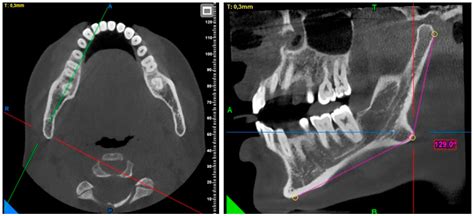

Diagnosing issues related to the mandible condylar process typically involves a combination of clinical examination, imaging studies, and patient history. Common diagnostic tools include:

• Imaging Studies: X-rays, CT scans, and MRI scans can provide detailed images of the mandible condylar process and surrounding structures, helping to identify fractures, deformities, or other abnormalities.